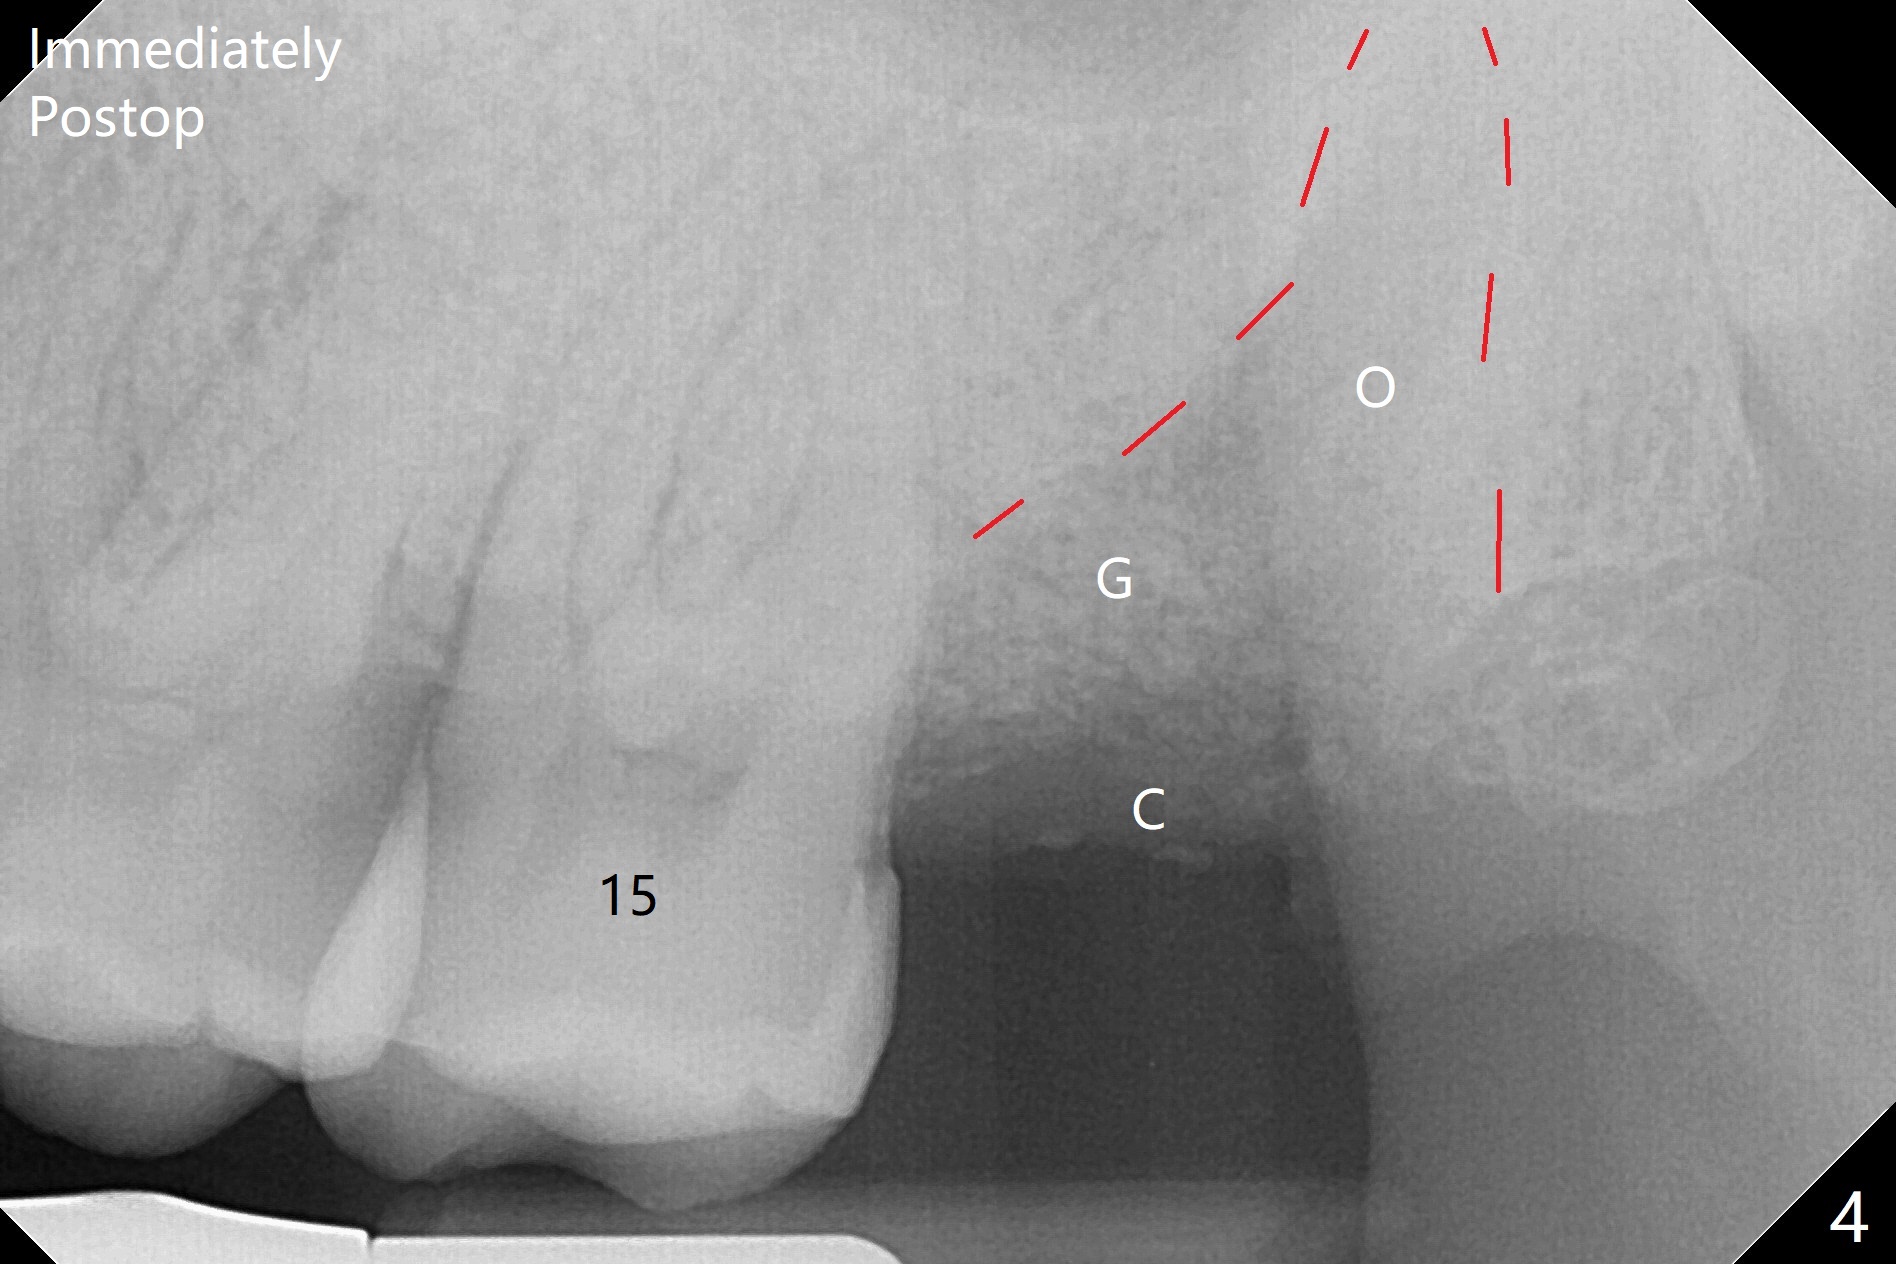

A 35-year-old woman requests extraction of the tooth #1 (food impaction between #1 and 2, Fig.1) and 16 (pain and 6 mm pockets between #15 and 16, Fig.2). In spite of the fact that there is bone loss between #14 and 15 (Fig.3), there is no deep pocket between them. After extraction of #16, SRP is performed in the distal surface of #15 with removal of granulation tissue and application of Endogain. Osteogen plug (Fig.4 O) is placed in the apical and distal portion of the socket of #16 (red dashed line), while allograft (G) against the distal root surface of #15. Finally Collagen plug (C) and 6-month membrane are placed in the opening of the socket, followed by suturing and periodontal dressing. The bone density is high post #1 extraction (Fig.6), related to difficult removal. It appears that bone graft at #16 (^) remains in place 15 months postop. Since no buccal trough is made for extraction, the external oblique ridge is present at #17 and 32 before and after surgery. Bond Apatite is placed with Collagen Plug (Fig.7).